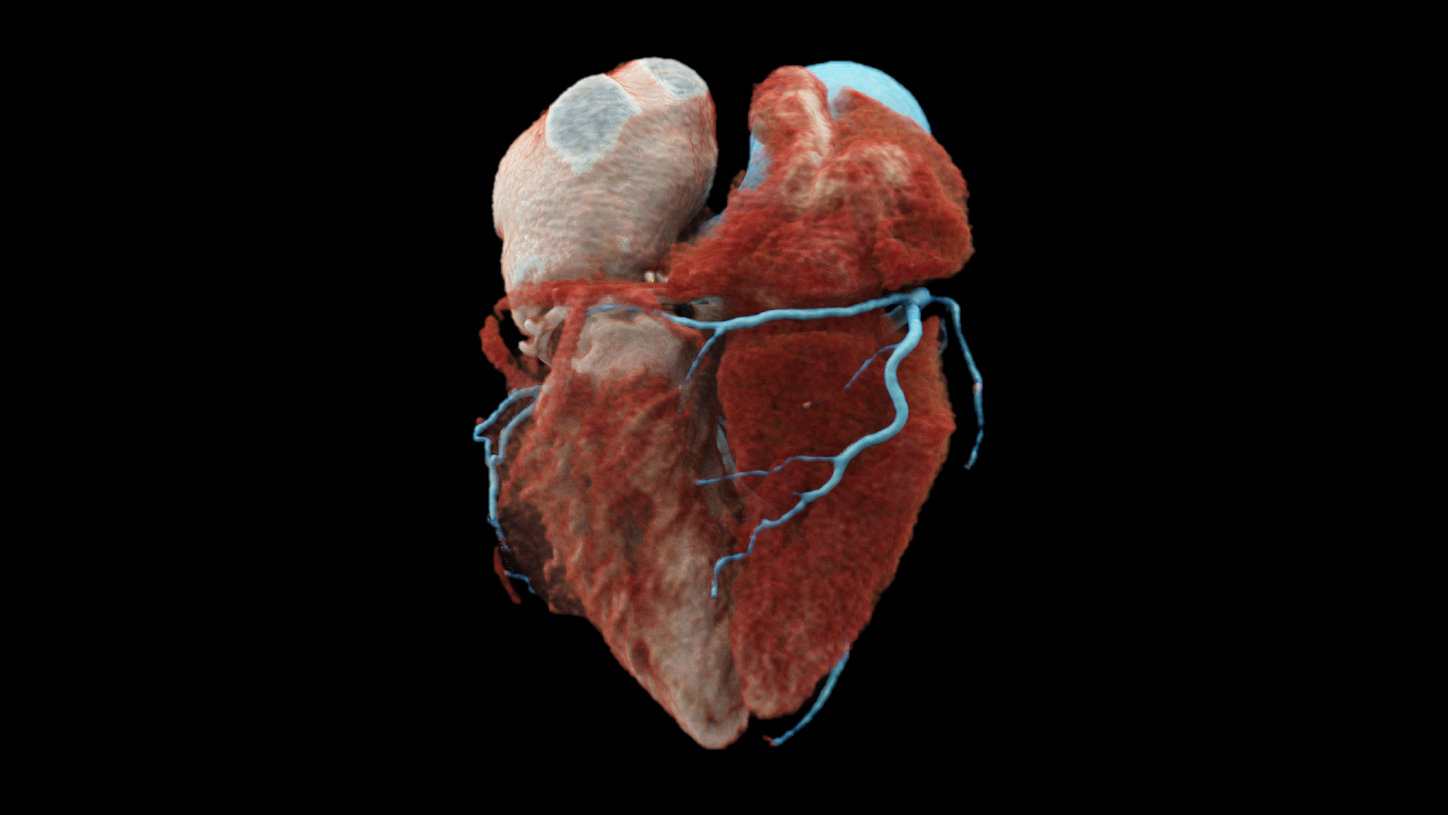

NAEOTOM Alpha

with Quantum Technology

NAEOTOM Alpha® offers high resolution in cardiac imaging to

- see small details in coronary CTA;

- identify more details in coronary plaque evaluation;

- offer high resolution at low dose in all standard CT angiography protocols.